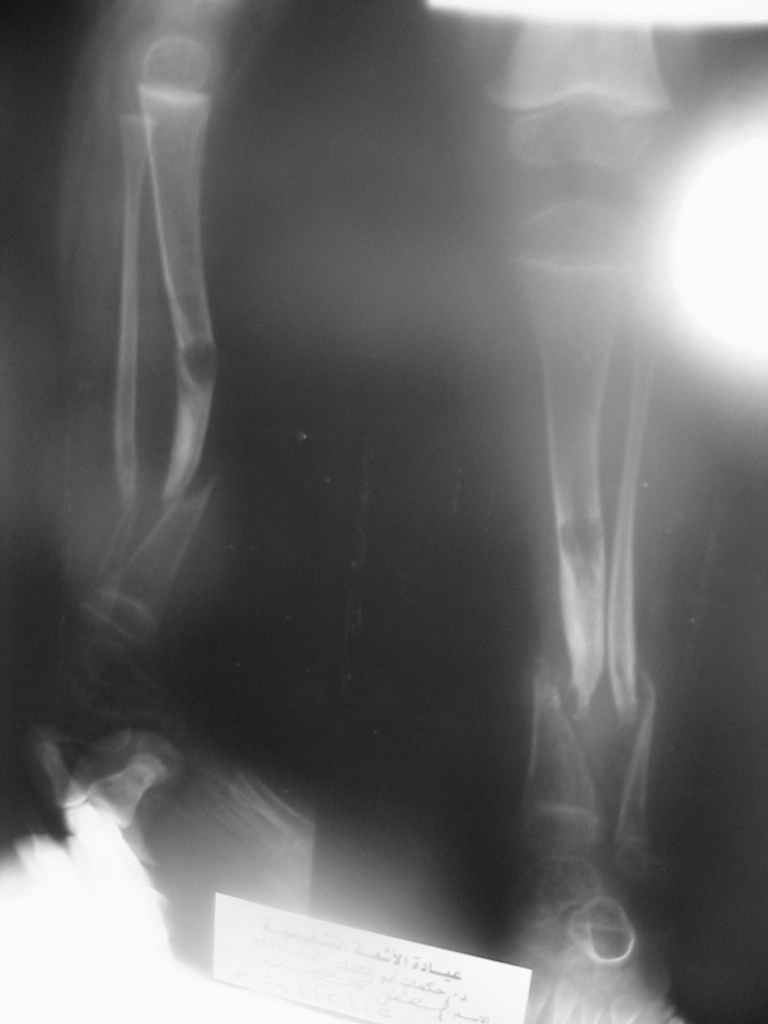

Uvazaemie Kollegy,Ko mne obratilsa malchik dva s polovenoi goda, stradaet ot vrozdennogo loznogo sustava N-3 kostei goleny,

Kakie budut soobrazenjia po planu ego lechenjia? Sposibo vsem za raneeCastro

А почему нейрофиброматоз? По представленной рентгенограмме определяется перестройка костной ткани берцовых костей, соответствующая системному заболеванию костной ткани - фиброзной дисплазии, предлагаемое И.Г. Лагуновой название данной нозологической формы - "диспластическая ангуляция голени". Изменения концов костных фрагментов протекают по типу нейротрофического остеолиза, возникающего, как считается, вторично, на фоне деформации голени. Этим объясняют особенности зоны перестройки и отсутствие репарации при хирургической коррекции. Применяемый термин "врожденный псевдоартроз голени" не отражает сущности процесса - торможения развития всех компонентов диафиза на этапе закладки первичных мезенхимальных зачатков. То есть оставшаяся вне зоны дефекта костная ткань так же неполноценна и срастить ее с трансплантатом будет проблематично.

Diagnos Neurofibromatosis, byl postavlen etomu rebenku davno, ne tolko na osnovanii rentgenologicheskoi kartiny kostei goleny, no i na osnovanii nalichiya ryada drugih priznakov i projiavlenii zabolevaniya, v t.ch. piatna "cafe-au-lait spots", i neurofibromatoznie uzly pod kozhei, i nasledstvenny anamnesis, i, nakonets, vrozdenny pseudoartrosis "to chto Vi vidite na snimkah", vot pochemu ne stavili Vash diagnos.

A chto kasaetsa Termina vrozdenny pseudoartros, to ortopedy ego ispolziot dla oboznachenjia riada pohozheih sostianii, nezavisimo ot prichiny vozniknovenjia etogo sostianiya!